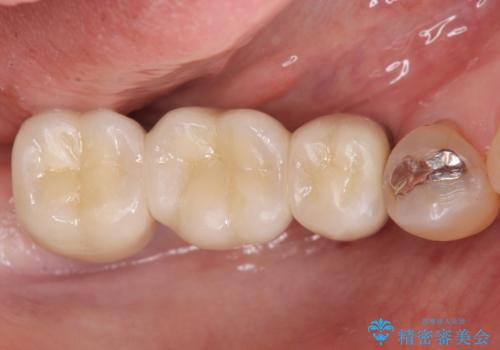

しっかりと咬むことができるようになり喜んで頂けました。

全体的な歯の動揺もなくなり安心して頂けました。

4年経過しましたが問題なく調子が良いとおっしゃって下さいました。

被せ物の種類:メタルボンドクラウン エコノミー

インプラントの種類:スプラインツイスト